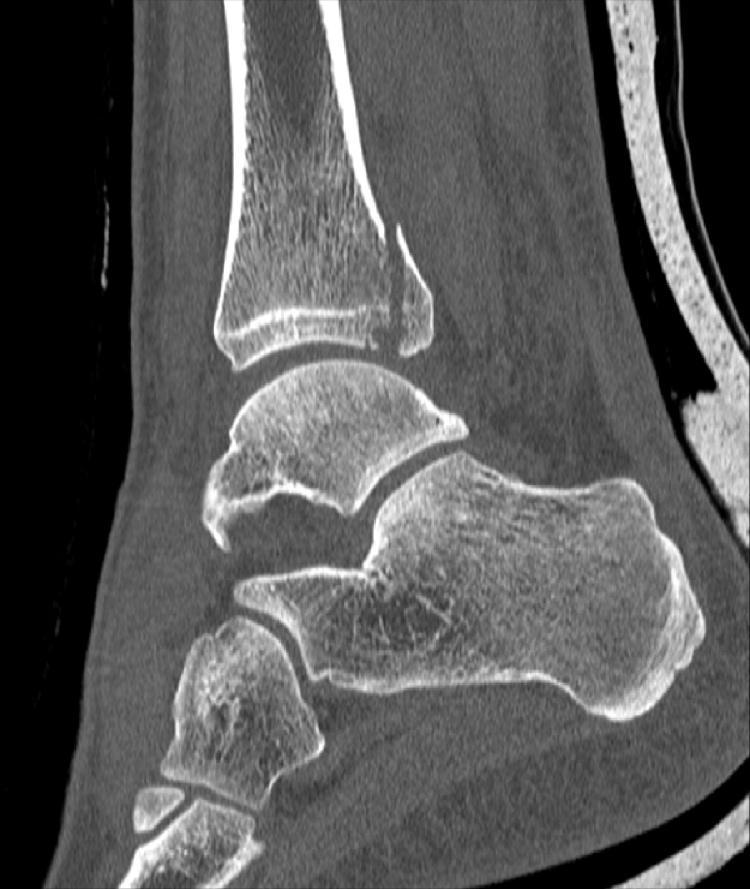

This case report and literature review shows that isolated posterior malleolar fractures might occur as part of a more complex ankle injury, in combination with a fracture of the lower leg or after high energy trauma. Physicians should be aware of these associated injuries. Diagnostic work-up should include X-rays of the knee and lower leg and a CT scan of the ankle. If diagnosed and treated properly, isolated posterior malleolar fractures have a good long-term functional outcome.

本病例报告及文献综述表明,孤立性后踝骨折可能作为更复杂踝关节损伤的一部分出现,与小腿骨折合并发生或在高能创伤后出现。医生应了解这些相关损伤。诊断检查应包括膝关节和小腿的 X 光片以及踝关节的 CT 扫描。如果诊断和治疗得当,孤立性后踝骨折具有良好的长期功能预后。